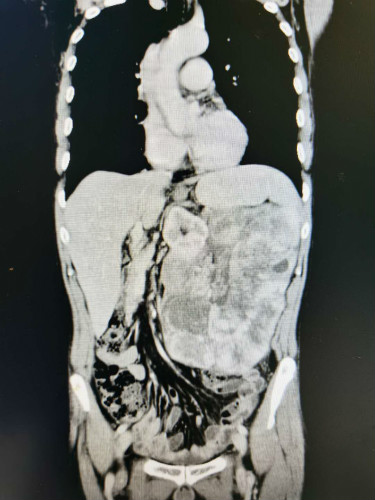

患者全腹CT

湖南湘阴的周先生因腹胀半月,在当地医院的CT检查结果显示腹膜后占位,考虑腹膜后肿瘤。当地医生建议,此手术难度大、风险高,建议到上级医院寻求最佳治疗。

8月31日,由吴君辉和田步宁医生等组成的手术团队为该患者实施了手术,开腹探查腹腔,发现瘤体大小约为:26*17*8cm,瘤体的体积太大直接导致各器官的血管及组织解剖结构发生改变,这大大增加了手术的难度,超过了预期所判。面对手术中遇到的种种困难,胃肠外科手术团队并没有放弃,继续攻坚克难,凭借着丰富的临床经验及精湛的手术技能,经过近四小时的鏖战,最终将约五斤重的肿瘤完整切除。